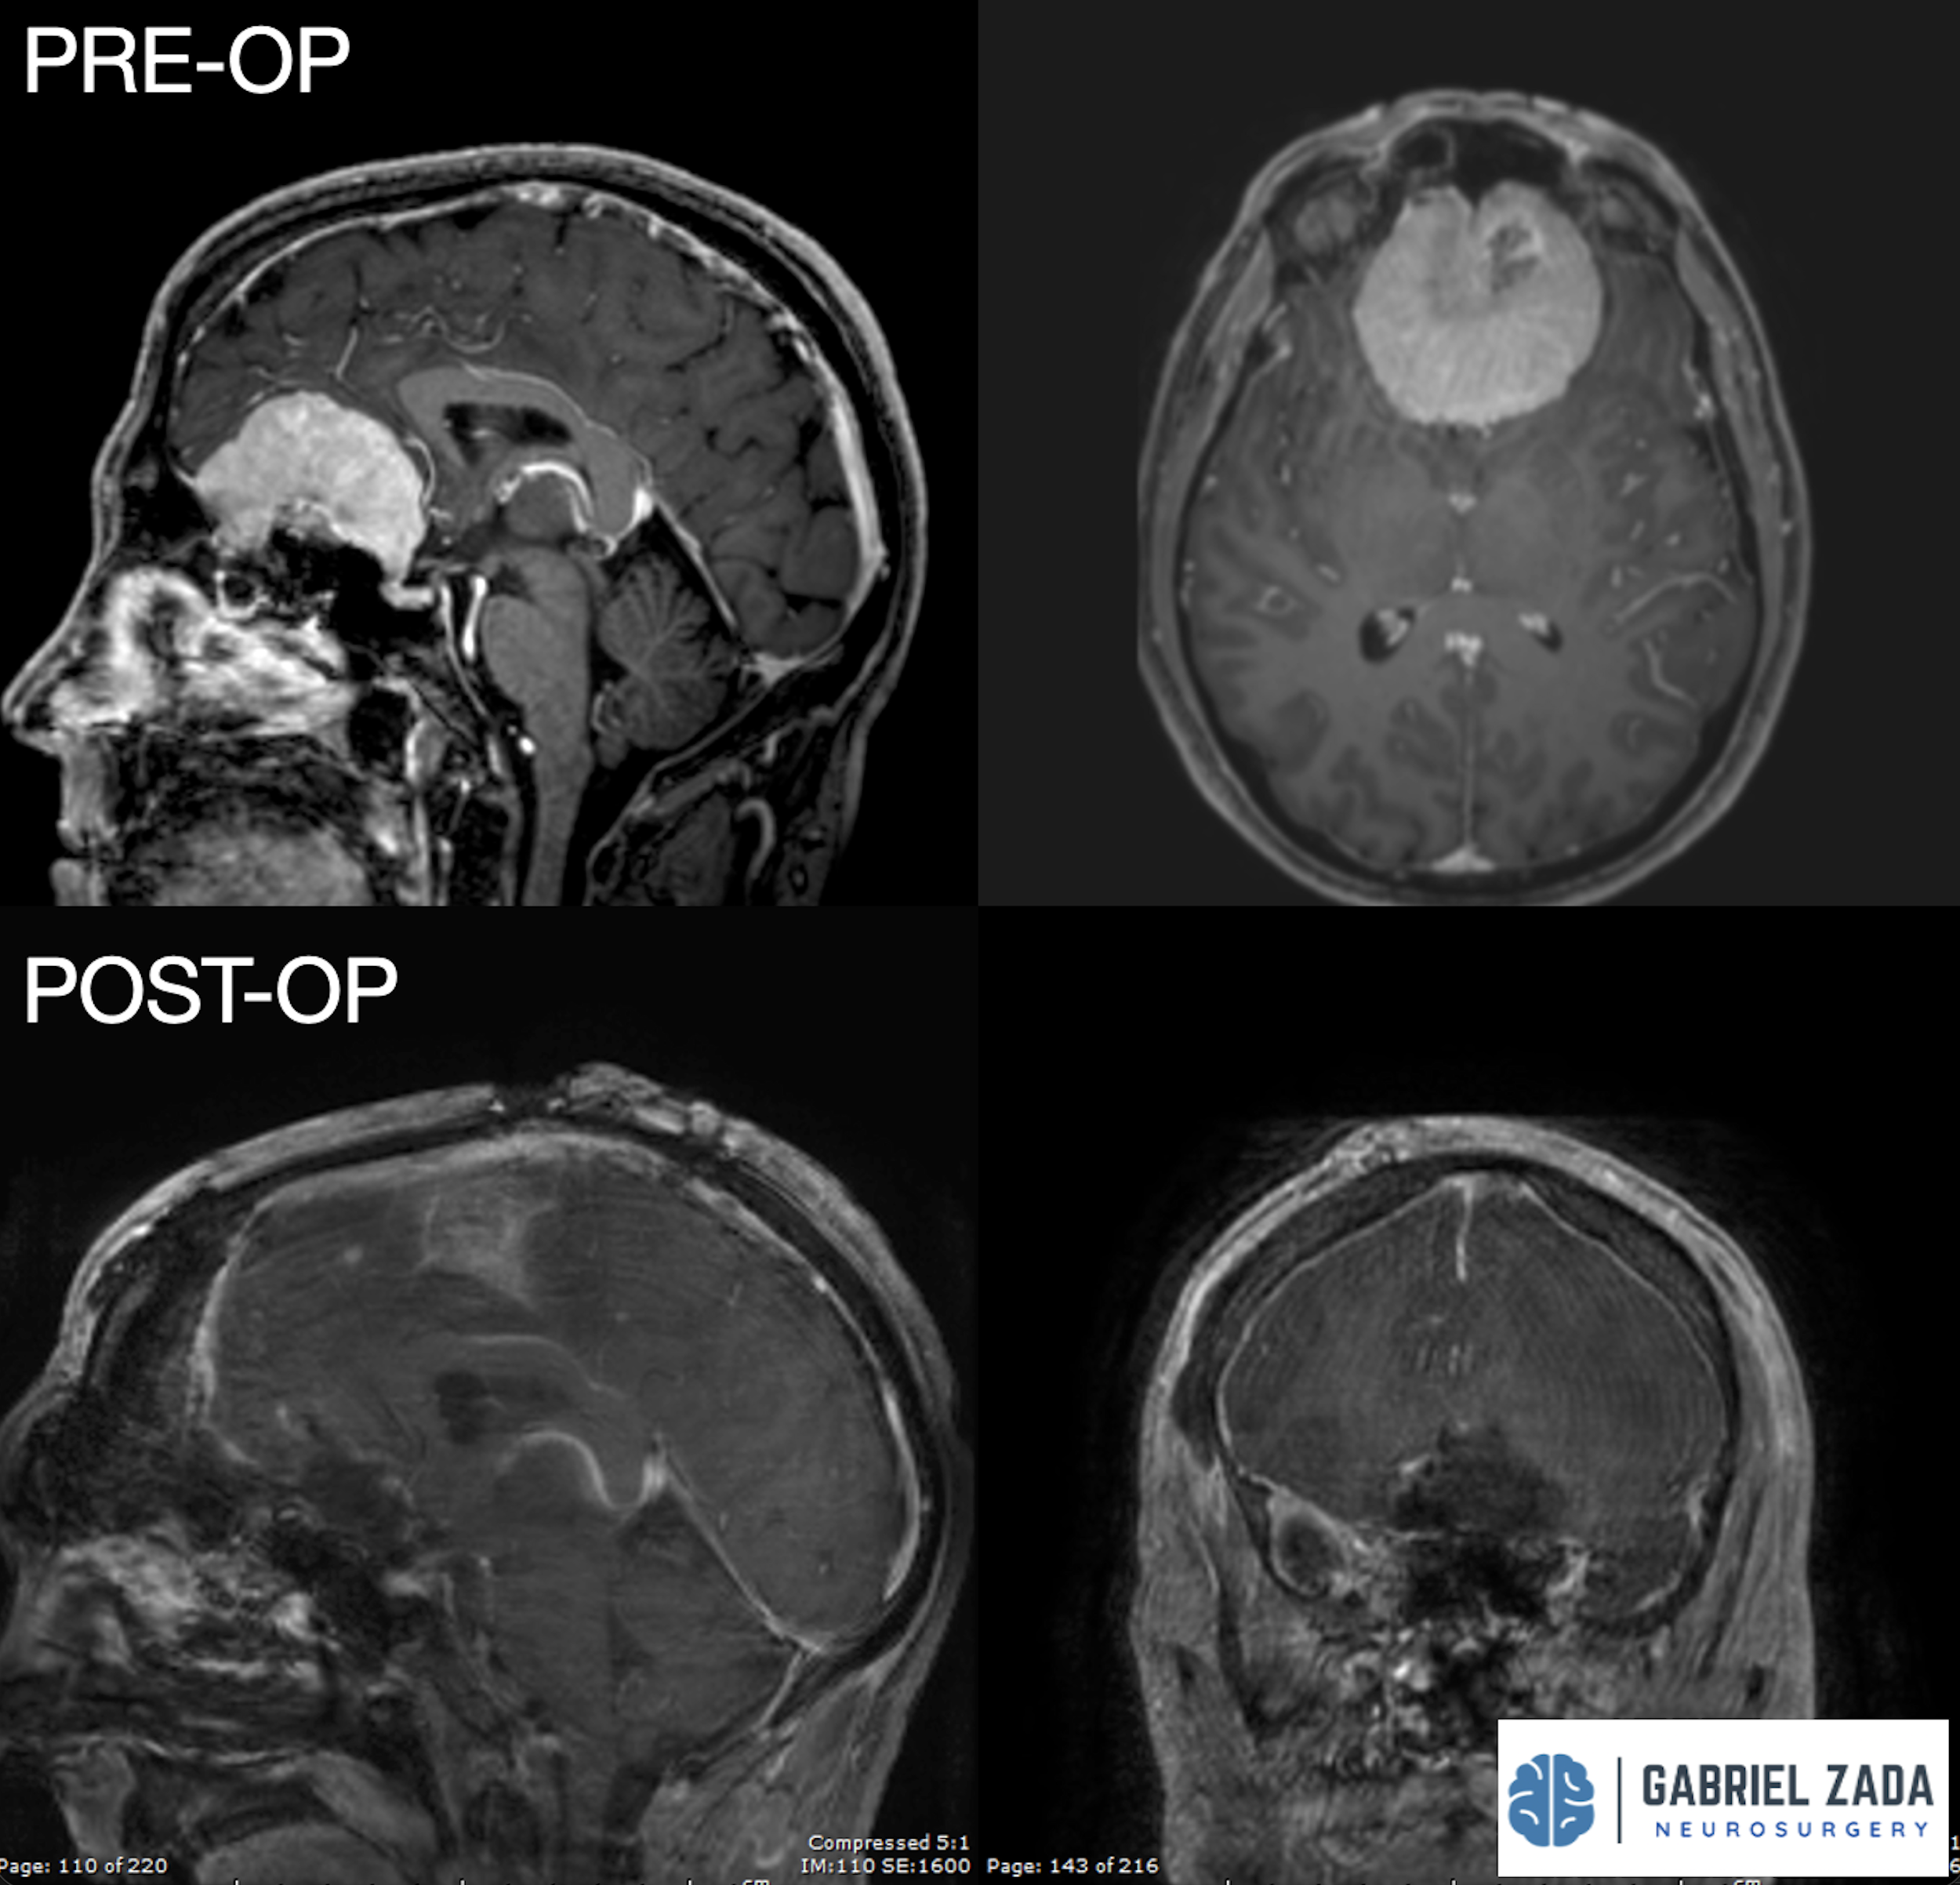

Explore this comprehensive gallery featuring pre‑ and post‑operative imaging of patients with skull‑base tumors treated by Gabriel Zada, MD, MS, FAANS, FACS. These cases highlight Dr. Zada’s expertise in advanced neurosurgical techniques and outcomes.

*Representative cases shown for educational purposes. All images de-identified. Individual results vary.